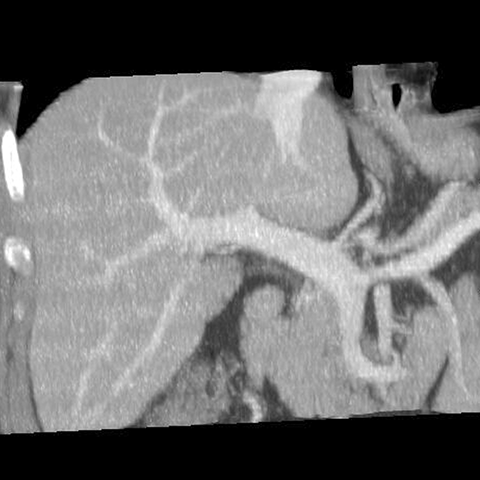

Normal Liver, CT ( coronal ) [4 of 5]